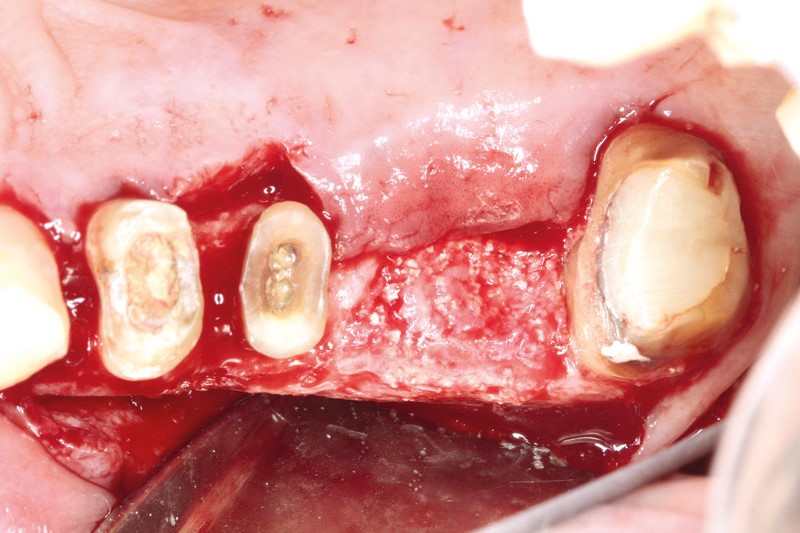

botiss-cerabone-permamem-maxgraft-mucoderm-horizontal-gbr-maghaireh

Initial situation - A young female 34 years old lost her front teeth in an surfing accident and she had a 5 unit bridge supported by her upper left lateral and right canine. The restoration failed and both supporting crowns have exposed and leaking margins.